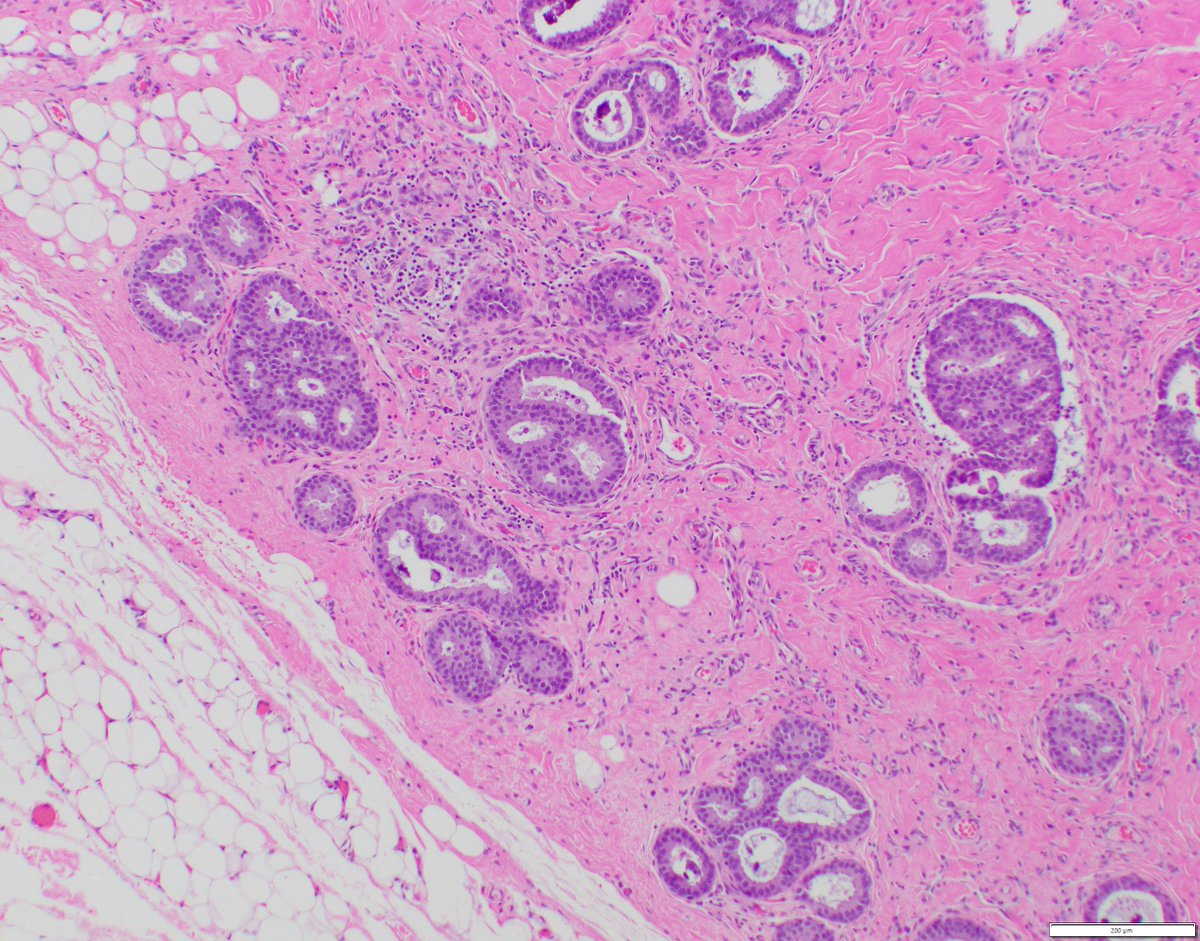

The correct answer is Salivary gland-type breast cancer: Adenoid Cystic Carcinoma, Solid-basaloid type, a TNBC characterized by solid growth pattern with a basaloid appearance and a translocation resulting in an MYB::NFIB fusion gene and the overexpression of MYB.